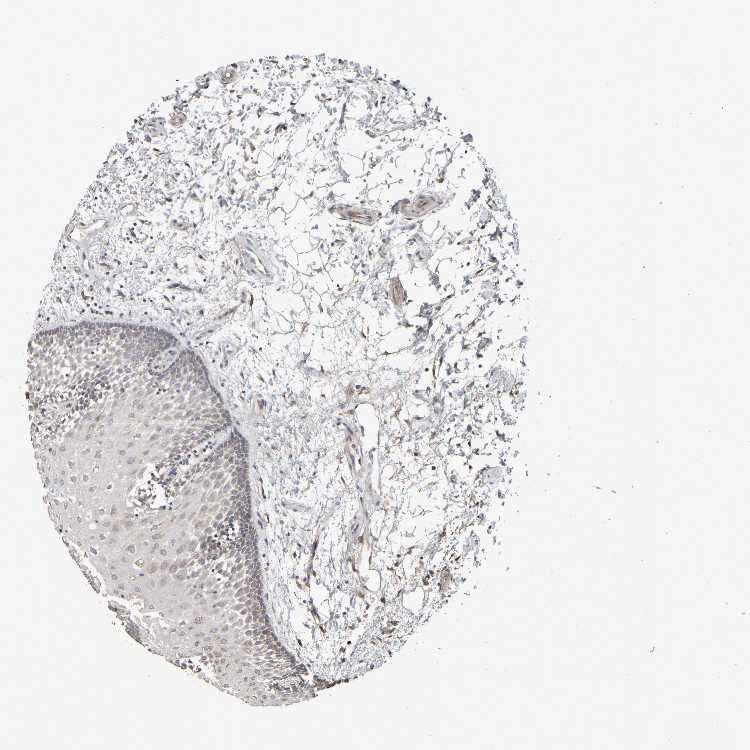

TISSUE PRIMARY DATA ORAL MUCOSA Show tissue menu

ORAL MUCOSA - Antibody stainingi

Antibody staining in the annotated cell types in the current human tissue is reported as not detected, low, medium, or high, based on conventional immunohistochemistry profiling in selected tissues. This score is based on the combination of the staining intensity and fraction of stained cells.

Each image is clickable and will lead to virtual microscopy that enables deeper exploration of all samples and also displays staining intensity scores, fraction scores and subcellular localization as well as patient and tissue information for each sample.

Antibody HPA020973Antibody HPA020987Antibody HPA021021

Squamous epithelial cells Not detectedNot detectedLow